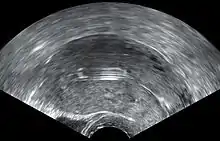

![]() Correctly inserted IUD | |